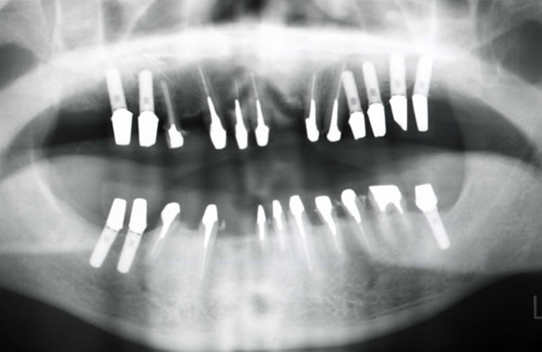

治療後

上下左右の奥歯はインプラント治療を行いました。しっかりとした固定製になり何でもよく噛めるそうです。前歯は歯周病の進行で、保存できない歯は抜歯、残せた歯は歯周治療を行い、固定製のセラミックブリッジにて治療しました。審美的にも機能的にも患者さんは大満足だそうです。